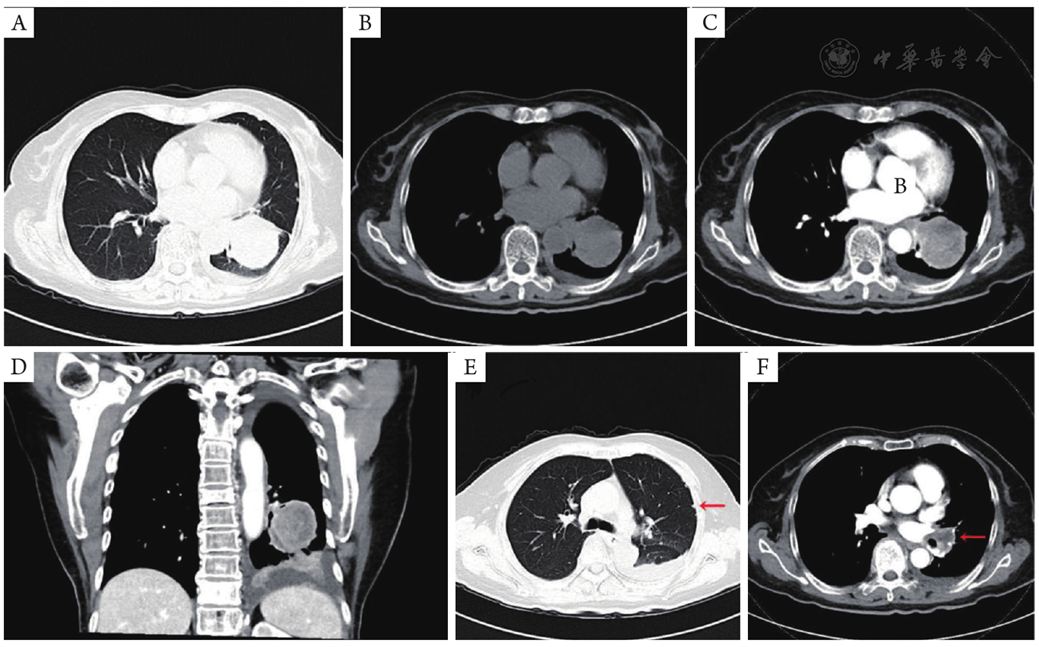

图9 全腹部增强CT(2025年04月10日):肝右叶转移瘤(A;红色箭头)及左侧肾上腺转移瘤(B;红色箭头)明显缩小。CT:计算机断层扫描